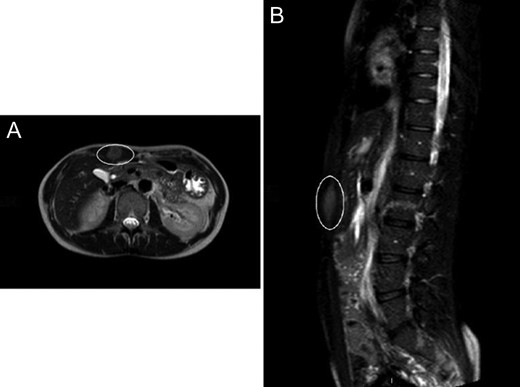

A 37-year-old female, otherwise healthy patient, presented to observation with a 3-month history of a mass in the upper right side of the abdomen, which has been gradually increasing in size, and no other associated symptoms. Past medical history was remarkable for atrial septal defect closure at the age of ten, but no previous abdominal surgeries or trauma. Patient did not smoke, drink alcohol or took any medication. During the physical examination, inspection showed a tattoo on the right side of the umbilicus (Fig. 1A); palpation at the same level revealed a painless and firm mass of 5 × 4 cm2 approximately, with not easily definable edges. Ultrasonography showed a 4 cm2 mass with no clear margins. Abdominal magnetic resonance (MRI) was subsequently performed describing a 17 × 19 × 50 mm3 mass confined into the rectus abdominis (Fig. 2A and B). Needle biopsy samples were taken, and pathology report confirmed the diagnosis of a desmoid tumour.

(A) Abdominal CT showing the desmoid tumour within the abdominal wall. (B) Abdominal CT scan showing lateral view of the desmoid tumour.